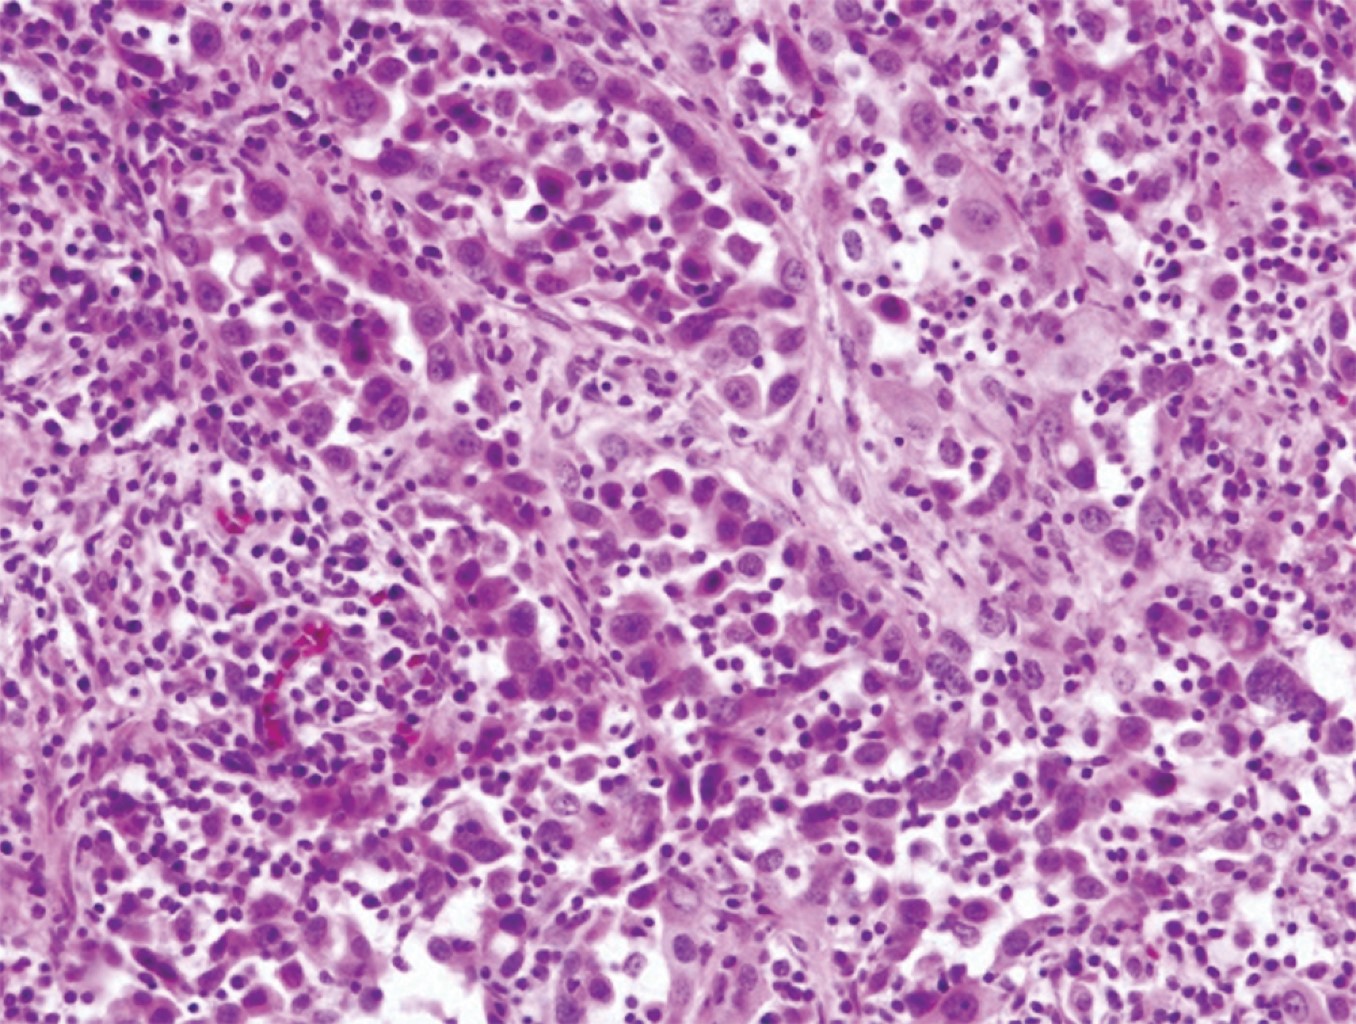

Dados los hallazgos y la alta sospecha de lesión tumoral, se realiza una biopsia guiada por TAC de la espinosa de T1 y del cuerpo vertebral de L2, siendo el resultado de estas biopsias negativo. Se decide programar una biopsia abierta en quirófano bajo control por escopía, siendo compatible el resultado en esta ocasión con el de un adenocarcinoma pulmonar (Figura 3).

Figura 3